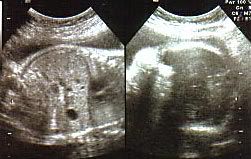

He's only around 4 mths old.

Hmm... don't know what I am looking at.

Ok here he is when he is 6 mths.

Ok now I can see him better.

This was when he is 7 mths.

Now I can see his eyes, nose and body. Ello Adik Fitri.

Ibu says Adik Fitri will come out in Nov. And ibu says he is always naughty because he likes to kick and make her tummy painful. "Adik Fitri jangan naughty, nanti ayah marah tau!" :)